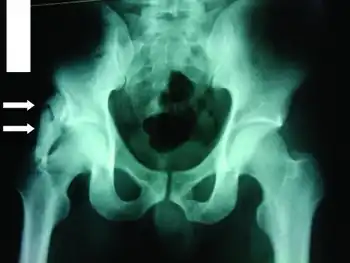

Most (i.e. 80%) ossifications arise in the thigh or arm, and are caused by a premature return to activity after an injury. Other sites include intercostal spaces, erector spinae, pectoralis muscles, glutei, and the chest. On planar x-ray, hazy densities are sometimes noted approximately one month after injury, while the denser opacities eventually seen may not be apparent until two months have passed.

The radiological features of myositis ossificans are ‘faint soft tissue calcification within 2–6 weeks, (may have well-defined bony margins by 8 weeks) separated from periosteum by lucent zone and on CT, the characteristic feature is peripheral ossification’.[10][11][12]